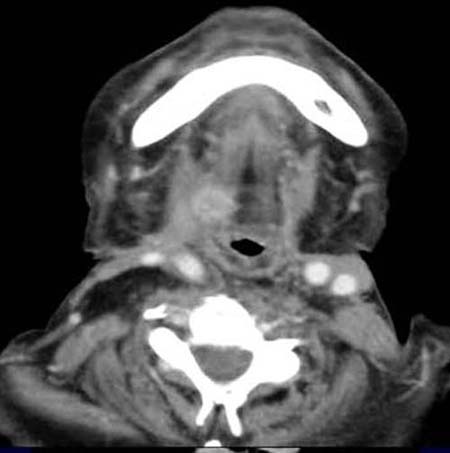

Patient mit Z.n. primärer Radio-Chemotherapie eines Plattenepithelkarzinoms

im Bereich des rechten Oropharynx.

Im

Mundboden rechts kommt im CT eine kontrastmittelaufnehmende

Raumforderung zur Darstellung. Z. n. Dissektion auf der rechten Seite.

Plattenepithel-Karzinom

Rezidiv